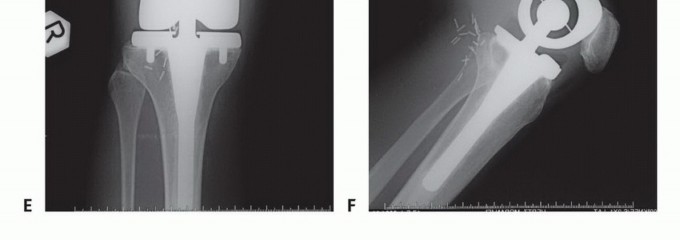

استبدال المفصل (Arthroplasty):

- الوصف: إذا كانت النقائل تؤثر على مفصل الورك أو الركبة، فقد يتم استبدال المفصل بأكمله بمفصل اصطناعي.

- الاستخدام: عندما تكون النقائل قريبة جدًا من المفصل وتؤثر على وظيفته بشكل كبير.

- ميزاته: استعادة كاملة لوظيفة المفصل وتخفيف الألم بشكل فعال.